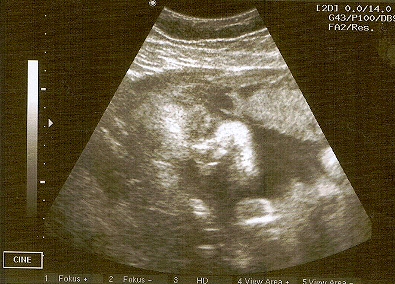

Das tanzen unsere Jüngsten im Mutterleib (=Feten). Dafür ist eine

entspannte“ mütterliche Umgebung nötig, da die Gefahr des

Überhitzens besteht (Mutter ist ruhig=das Kind hampelt,

Mutter hat Stress=das Kind ist ruhig, antagonistisches Muster!). So weit es

ihnen möglich ist, tun sie das auch noch in den ersten 6 Monaten nach

der Geburt – dann stört allerdings die Schwerkraft.